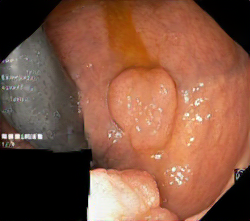

We have used a polyp dataset published with HyperKvasir dataset [51], which consists of polyp findings extracted from endoscopy examinations. HyperKvasir contains polyp images with corresponding segmentation masks annotated by medical experts. We use only this polyp dataset as a case study because of the time and resource-consuming training process of the SinGAN-Seg pipeline. However, the SinGAN-Seg model and pipeline can be used for any segmentation dataset.

A few sample images and the corresponding masks of the polyp dataset in HyperKvasir are shown in Fig 2. The polyp images are RGB images. The masks of the polyp images are single-channel images with white () for true pixels, which represent polyp regions, and black () for false pixels, which represent clean colon or background regions. In this dataset, there are different sizes of polyps. The distribution of polyp sizes as a percentage of the full image size is presented in the histogram plot in Fig 3, and we can observe that there are more relatively small polyps compared to larger polyps. Additionally, a subset of this dataset was used to prove that the performance of segmentation models trained with small datasets can be improved using our SinGAN-Seg pipeline, and the whole dataset was used to show the effect of using SinGAN-Seg generated synthetic images instead of a large dataset which has enough data to train segmentation models. In this regard, this dataset was used for two purposes: